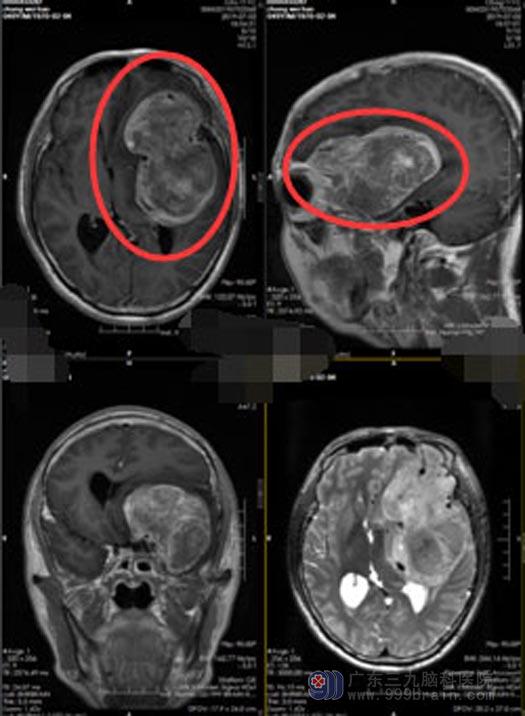

老张立马联系了家人,当地医院头颅MR检查,提示“左侧额颞顶叶巨大占位性病变,考虑胶质瘤可能”,当地医院处理不了,建议转上级医院。家人得知可能是恶性肿瘤时,都吓傻了。

来到神经外五科,老张做了更详细的检查后,鲁明副院长考虑他良性脑膜瘤可能性更大一些,但肿瘤的体积巨大,直径有8cm左右,血供丰富,颅内多条粗大的血管被肿瘤包绕,并且是位于左侧优势半球,手术对老张的语言功能可能会有影响。